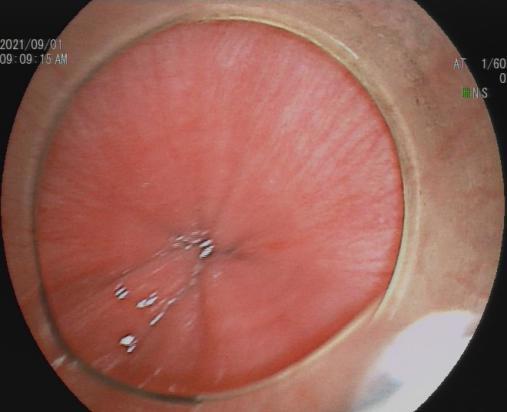

九、经口内镜下食管括约肌切开术(peroralendoscopicmyotomy,POEM)

POEM是治疗贲门失弛缓症的内镜新技术,基本取代传统的胸外科开胸食管肌切开术,成为首选的治疗方式。

贲门失弛缓症食管紧闭 食管粘膜切开建立隧道

食管肌切开 金属夹闭合切口